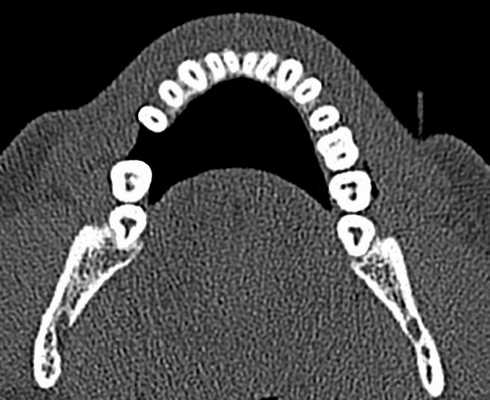

Описаны варианты раздвоения канала нижней челюсти (НЧ), которые были выявлены как случайные находки при конусно-лучевой компьютерной томографии челюстно-лицевой области пациентов, обращавшихся в медицинские центры за стоматологической помощью. Выявленные добавочные каналы в теле НЧ начинались от верхней стенки нижнечелюстного канала и имели небольшую протяженность. Они заканчивались в ретромолярной области, направлялись к корням зубов или ориентировались параллельно основному каналу НЧ.

Удвоение канала нижней челюсти — НЧ (нижнечелюстного канала) — вариант его анатомического строения. О нем имеется упоминание в национальном руководстве по хирургической стоматологии и челюстно-лицевой хирургии [1], а также в ряде научных статей, авторы которых обнаружили дополнительный канал (ы) на анатомических препаратах [2, 3]. Частота выявления нескольких каналов НЧ при анализе ортопантомограмм (ОПМГ) — 0,08—0,95% [4]. Конусно-лучевая компьютерная томография (КЛКТ) выявляет наличие раздвоенного канала в 15,6—64,6% случаев [5—7]. В соответствии с классификацией M. Naitoh и соавт. [5] различают 4 типа канала (рис. 1). Рис. 1. Конфигурация раздвоенного канала НЧ (по M. Naitoh и соавт. [5]). 1-й тип: передний канал — дополнительный канал сливается с основным (а) или оба они идут параллельно (б); 2-й: щечно-язычный канал — расположен со щечной (в) или язычной (г) стороны от основного канала; 3-й: дентальный канал — ведет к корням зубов (д); 4-й: ретромолярный канал — заканчивается ретромолярным отверстием в одноименной ямке (е).

Рентгенологическое исследование проводилось на аппарате Galileos GAX5 («Sirona Dental Systems, Bensheim», Germany). Анализ полученных данных проводился по традиционной методике, предусматривающей последовательное изучение сначала срезов в 3 взаимно перпендикулярных проекциях (окно мультипланарной реконструкции), затем срезов, расположенных продольно и поперечно относительно зубной дуги (в окне «Панорама»), а также томограмм произвольной кросс-секции, оптимальной для получения изображений анатомических объектов соответственно их пространственному положению. Оптимальными для визуализации вариантов ветвления канала НЧ являлись реформаты вдоль продольной оси ее тела, которые обозначаются по терминологии разработчиков аппарата как «касательные».

Ниже представлены описания рентгенологической картины раздвоенного канала НЧ 3 типов.

Пациентка Е., 48 лет. С левой стороны на уровне угла НЧ от нижнечелюстного канала отходила боковая ветвь (рис. 2). Рис. 2. Ретромолярный канал; КЛКТ пациентки Е., 48 лет. 1 — канал НЧ; 2 — ретромолярный канал; 3 — подбородочное отверстие. Ее поперечный диаметр составлял 1,37 мм у места начала и 0,96 мм в области ретромолярного отверстия.

Поперечный диаметр канала НЧ у места начала ветви — 3,08 мм. Сначала дополнительный канал направлялся вперед. На расстоянии 5,33 мм от места бифуркации он образовывал петлю, менял направления хода и шел назад и вверх, заканчиваясь отверстием в ретромолярной области. Описанный ход характерен для ретромолярного канала (4-й тип раздвоенного канала НЧ). На контралатеральной стороне дополнительных каналов НЧ не обнаружено.

Пациентка Ф., 55 лет. С правой стороны на уровне угла челюсти от верхней стенки нижнечелюстного канала начинался дополнительный канал с поперечным диаметром 1,52 мм (рис. 3, а). Рис. 3. Дентальный канал нижней челюсти. а — КЛКТ пациентки Ф., 55 лет; б — КЛКТ пациентки К., 29 лет. 1 — канал НЧ; 2 — дентальный канал; 3 — подбородочное отверстие. Поперечный диаметр основного канала на этом же уровне — 2,70 мм. Дополнительный канал направлялся полого вперед и вниз параллельно основному каналу НЧ. В мезиальном направлении кортикализация стенок дополнительного канала постепенно уменьшалась, и достоверно проследить его ход удалось до уровня зуба 4.7. Описанная картина характерна для дентального канала (3-й тип раздвоенного канала НЧ). С левой стороны визуализация дополнительного канала была недостоверной: выявлялось линейное просветление такой же локализации и направления, как с правой стороны, но картины трубчатого образования не выявлено, вероятнее всего — вследствие недостаточной кортикализации его стенок.

У пациентки К., 29 лет, с левой стороны обнаружен дентальный канал (см. рис. 3, б). В месте отхождения он имел вертикальный диаметр 1,35 мм (приблизительно в 3 раза меньше вертикального диаметра канала НЧ на этом же уровне), направлялся вперед и вниз, располагаясь параллельно основному нижнечелюстному каналу, и на уровне медиального корня зуба 3.7 круто поднимался вверх. Дентальный канал переставал идентифицироваться на уровне средней трети корня второго нижнего левого моляра. С правой стороны раздвоения канала НЧ не выявлено.

Пациентка Б., 57 лет. С правой стороны на уровне угла НЧ определялась добавочная ветвь нижнечелюстного канала диаметром 1,1 мм, которая, начинаясь от его верхнего контура, далее шла вперед почти параллельно основному каналу на протяжении 8,01 мм, а затем сливалась с ним (рис. 5). Рис. 5. Конфигурация канала НЧ; КЛКТ пациентки Б., 57 лет. 1 — канал НЧ; 2 — передний канал. На контралатеральной стороне добавочных каналов не обнаружено. Описанная рентгенологическая картина соответствует 1-му (а) типу раздвоенного канала НЧ.

Канал НЧ при типичной локализации визуализируется в виде трубчатого костного образования, стенки которого представлены тонкими линейными затемнениями кортикальных пластинок, а содержимое канала отображается в виде интенсивного просветления. Калибр канала постепенно уменьшается в мезиальном направлении. Достоверным признаком наличия дополнительного канала является продолжение в его стенку кортикальной пластинки основного канала. Это дает возможность проследить дополнительный канал на всем его протяжении. У места его начала канал НЧ, как правило, имеет локальное расширение. Дополнительные каналы обычно отходят от верхней стенки канала НЧ и имеют небольшую протяженность.